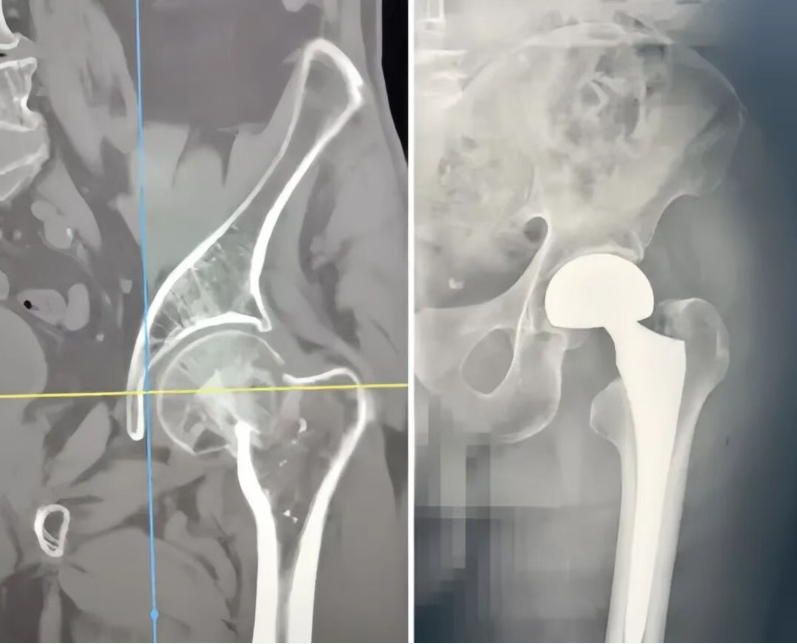

手术中,手术麻醉科团队为患者实施精准麻醉,确保手术侧麻醉效果良好,为手术安全筑牢关键基础;手术麻醉科与骨科团队全程紧密配合,顺利为患者开展双极股骨头置换术。

令人欣喜的是,手术十分顺利,术后第一天患者便能下地行走。摆脱长期卧床后,患者肺部及其他基础疾病也随之改善,不久便顺利出院。术后一个月电话回访时,家属欣喜告知:患者已能正常行走,生活基本自理。